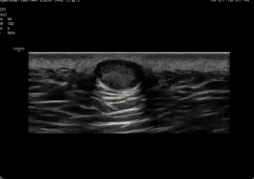

V7 GI

V7 GI – Ecógrafo para Diagnóstico General

El ecógrafo Samsung V7 GI está diseñado para ofrecer diagnósticos de alta precisión en aplicaciones generales, incluyendo abdomen, pediatría, vascular, urología y musculoesquelético. Combina Crystal Architecture™ con funciones inteligentes que aceleran el flujo de trabajo y permiten obtener resultados consistentes y confiables. Su diseño ergonómico y su interfaz intuitiva facilitan la práctica diaria de profesionales sanitarios en hospitales, clínicas generales y estudios especializados.

Aplicaciones principales: Diagnóstico abdominal, estudios pediátricos, evaluación vascular, exploración musculoesquelética, ultrasonido ginecológico y urológico.